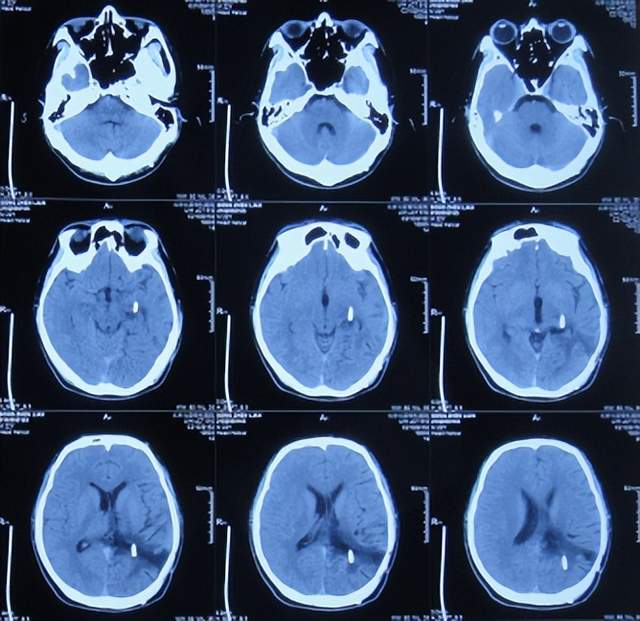

继续抗感染治疗1周的时间,仍精神差,食欲差,间断发热,期间3次查头颅影像(2021年1月29日头颅核磁增强(图-10)、2021年1月31日头颅CT(图-11)、2021年2月3日头颅核磁增强(图-12)均示颞角逐渐有扩张,有感染。

图-10:2021年1月29日头颅核磁增强

图-11:2021年1月31日头颅CT

图-12:2021年2月3日头颅核磁增强

脑膜瘤术后3周,间断发热2周,因治疗不见好转,且颞角稍有扩张,因此为了更专业的治疗,拔除腰大池引流管后转至北京北亚骨科医院的李小勇脑脊液科。

2021年2月5日(脑膜瘤切除术后颅内感染3周)住入李小勇脑脊液科,入院时:精神差,食欲差,体温高(图-13);查头颅CT示脑瘤术后状态(图-14);(外院)2021年2月3日头颅核磁示有脑脓肿(图-12)。

图-13:2021年2月5日入院时

图-14:2021年2月5日头颅CT

入院后3天即2021年2月8日,左颞角脑室腹壁外引流术(图-15)。

图-15:2021年2月8日头颅CT

左颞角脑室腹壁外引流术后8天即2021年2月16日,查头颅CT示颞角缩小(图-16)。

图-16:2021年2月16日头颅CT

左颞角脑室腹壁外引流术后21天即2021年3月1日,查头颅CT示颞角仍有扩张(图-17)。

图-17:2021年3月1日头颅CT

左颞角脑室腹壁外引流术后23天即2021年3月3日,头颅CT增强和核磁增强示有脑脓肿(图-18、图-19)。

图-18:2021年3月3日头颅CT增强

图-19:2021年3月3日头颅核磁增强

2021年3月8日(左颞角脑室腹壁外引流术后28天),进行了脑脓肿切除术(图-20)。

图-20:2021年3月8日头颅CT

2021年3月9日(左颞角脑室腹壁外引流术后29天,脑脓肿切除术后次日),查头颅CT示脑脓肿切除术后(图-21)。

图-21:2021年3月9日头颅CT

2021年3月11日(左颞角脑室腹壁外引流术后31天,脑脓肿切除术后4天),患者身体状态良好,体温变正常(图-22)。

图-22:2021年3月11日

2021年3月12日(左颞角脑室腹壁外引流术后32天,脑脓肿切除术后5天),查头颅CT示仍有少量水肿(图-23)。

图-23:2021年3月12日头颅CT